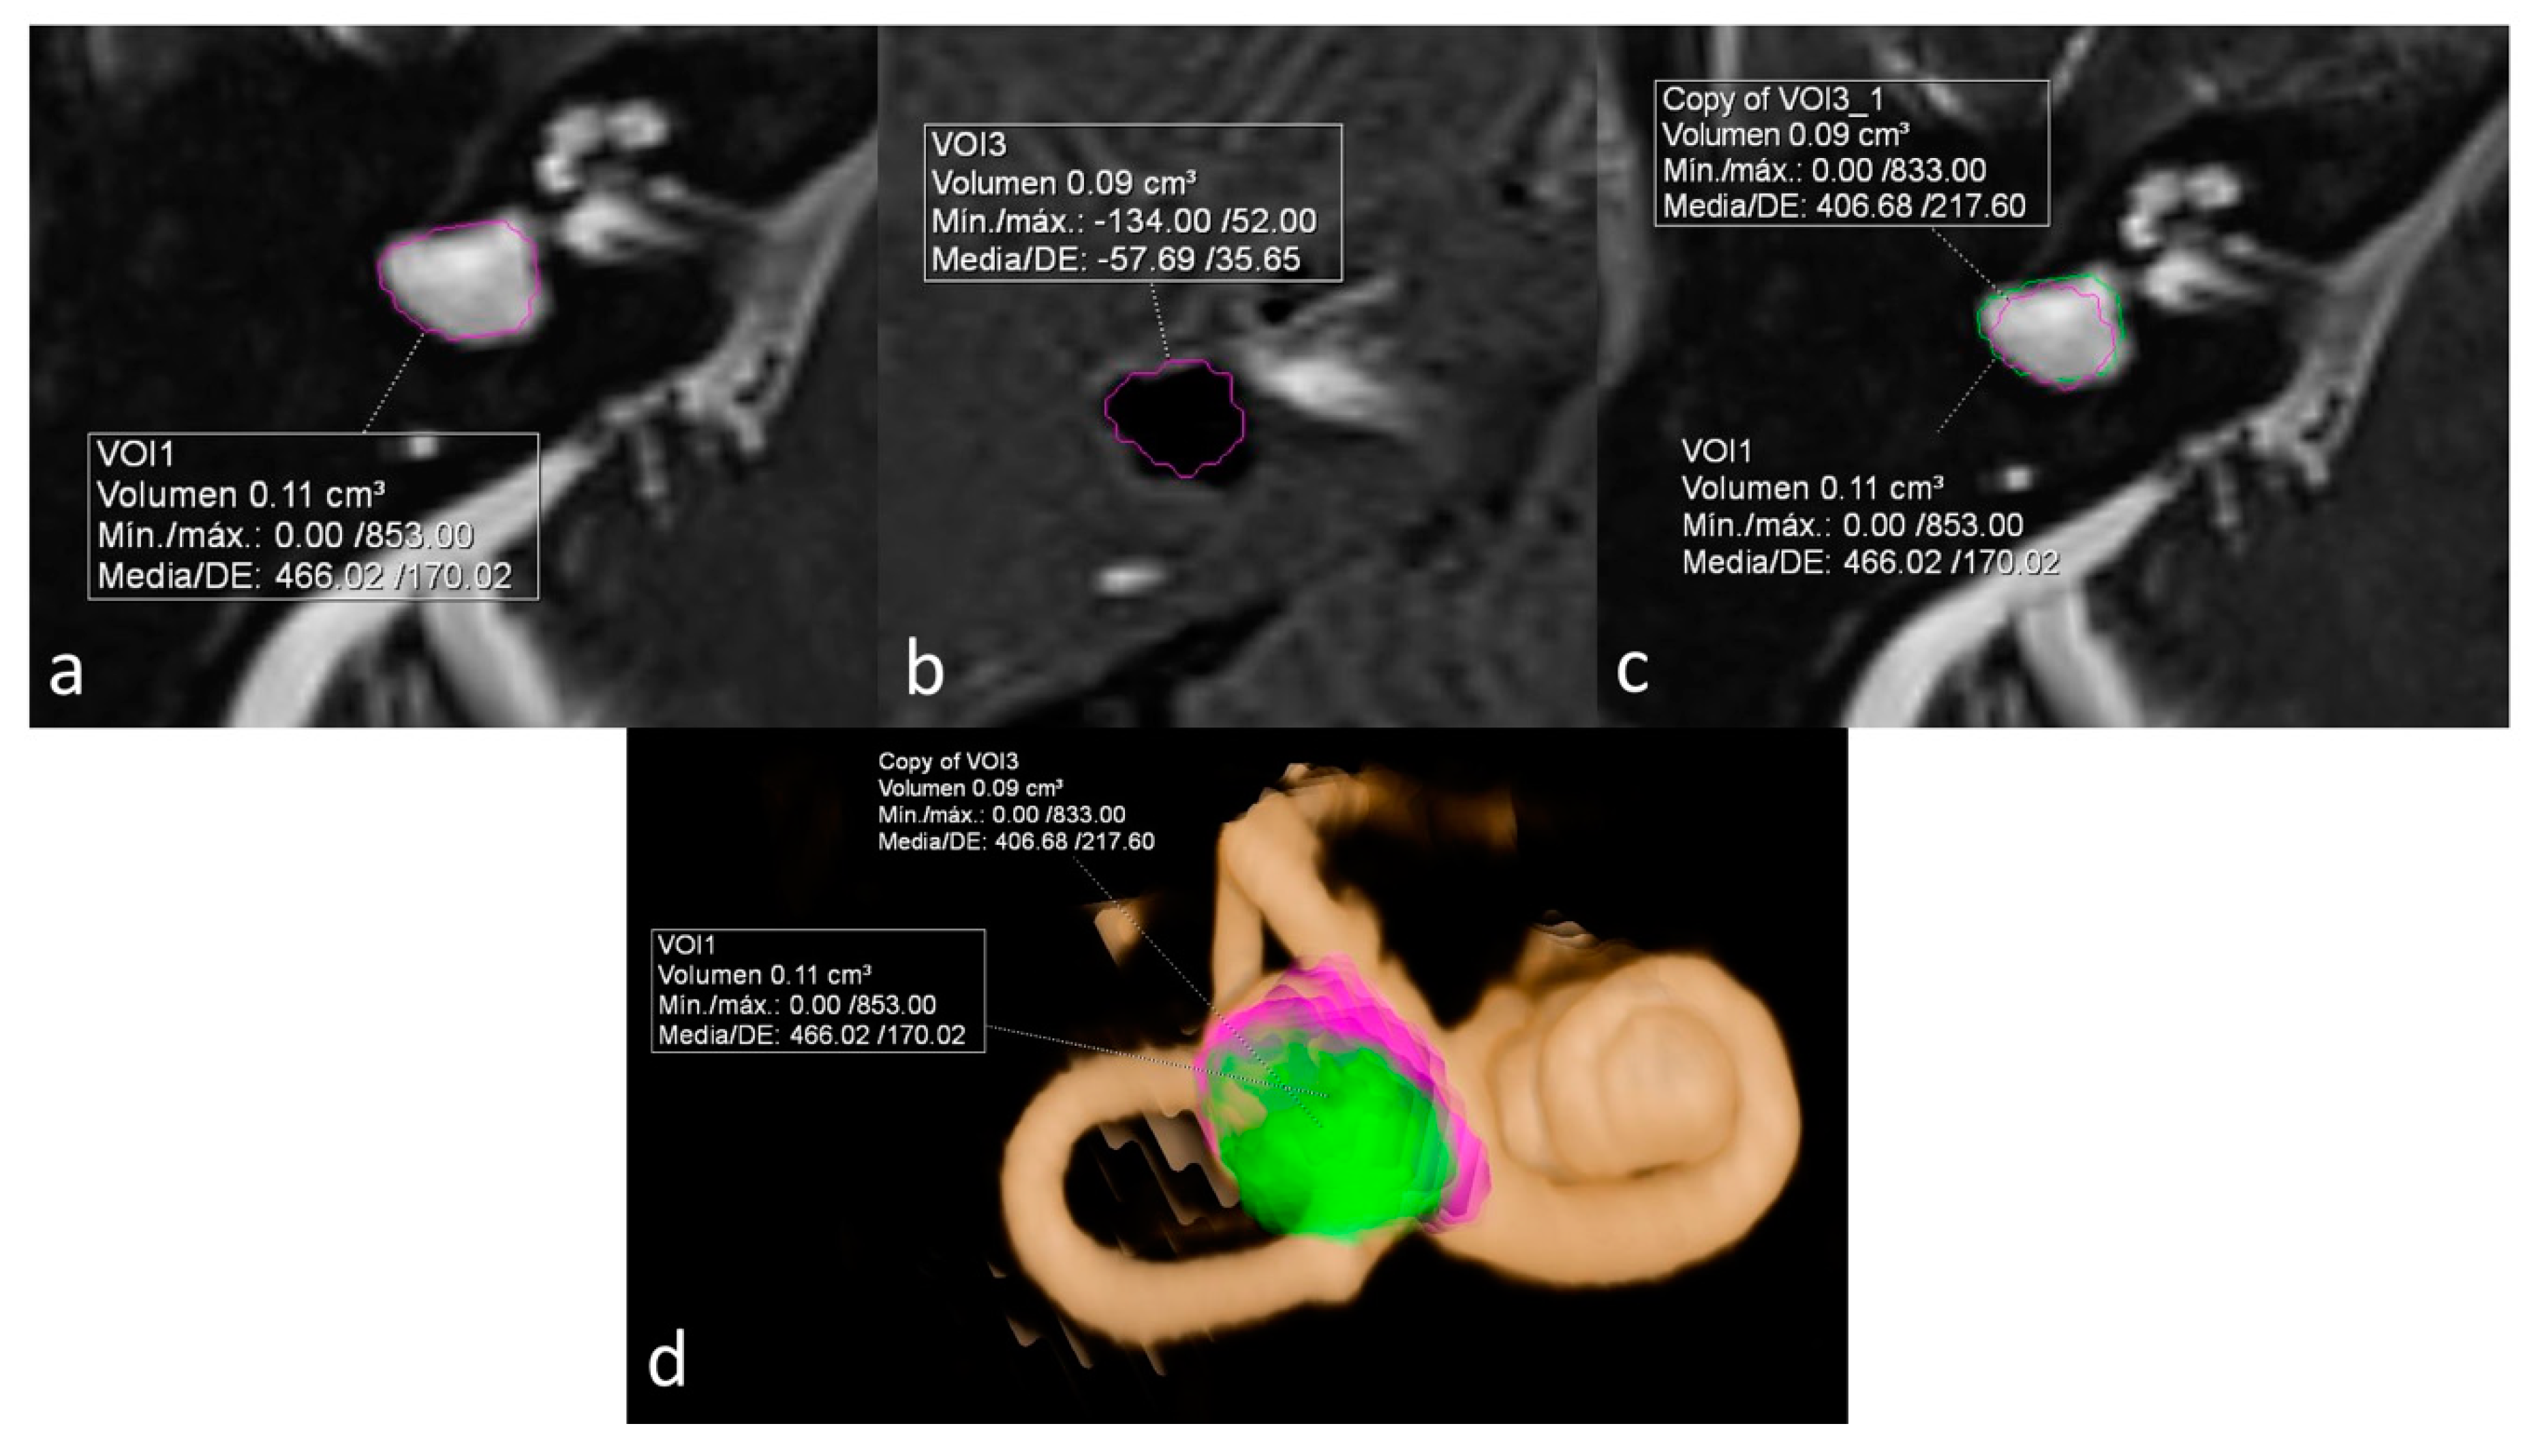

ELR ranged from 22% to 81%. It´s interesting to note that both extremes were present in the same patient, corresponding to a patient with right unilateral Ménière’s syndrome but with bilateral LSCCD (patient 4). On the dysplastic clinically affected side, ELR was 81% (Figure 2), whereas on the dysplastic clinically asymptomatic ear, ELR was barely 22% (Figure 3). In patients with unilateral LSCCD and available hydrops MR imaging (patients 3 and 5), the contralateral “normal anatomy” inner ear showed no signs of endolymphatic hydrops with endolymphatic ratios of less than 25% (not shown). The contralateral “normal anatomy” inner ear was asymptomatic.

Figure 2.

Patient with bilateral LSCCD. Right clinically affected ear. (a) Heavily T2 weighed cisternography sequence with total vestibular lymph volume. (b) 3D-IR-REAL hydrops sequence shows vestibular endolymphatic volume (dark signal). Note also cochlear hydrops. (c) Overlay of both volume values in the cisternography sequence for the calculation of the endolymphatic ratio (ELR). (d) 3D volume-rendered image of the inner ear with color coded overlay of both cisternal and vestibular hydrops volumes. ELR of 81% suggesting severe vestibular hydrops.